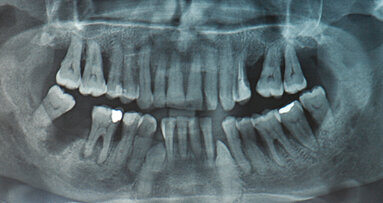

Un paziente di 61 anni, con storia medica non rilevante, è stato inviato nel nostro studio dal suo odontoiatra per il ritrattamento del primo molare inferiore. Il dente era sensibile alla percussione. In entrambe le radici e nell’area della forcazione era evidente una radio trasparenza periapicale. Più di dieci anni prima era stato eseguito un trattamento canalare. L’otturazione canalare risultava corta ed era presente un frammento di perno radicolare nel canale mesiolinguale (Figg. 1, 2). Il piano di trattamento consisteva nel restauro del dente con un perno fuso e una corona in metallo-ceramica (PFM).

Dopo aver somministrato l’anestesia locale, è stata applicata la diga di gomma ed è stata rimossa l’otturazione provvisoria. Il perno frammentato è stato rimosso mediante punte ultrasoniche sotto ingrandimento (G6, Global Surgical). A causa della vicinanza del perno alla forcazione, si è prestata attenzione a non rimuovere la dentina distale al perno. Anche il materiale di otturazione canalare apicale al perno e dagli orifizi degli altri canali radicolari è stato rimosso con punte ultrasoniche. L’osservazione a ingrandimento elevato mostrava una piccola perforazione della parete canalare dove era stato posizionato il perno (Fig. 3). Il paziente e il suo dentista sono stati quindi informati che il dente avrebbe dovuto essere ritrattato e il difetto di perforazione sigillato con cemento MTA (Dentsply Maillefer).

Per tutto il trattamento è stata utilizzata un’abbondante irrigazione (NaClO al 2,5%). I canali radicolari sono stati sagomati con una combinazione di frese Gates-Glidden e strumenti rotanti al NiTi. Ad alto ingrandimento, nella radice distale è stato trovato un ulteriore spazio canalare (Fig. 4). I residui della precedente otturazione canalare sono stati rimossi mediante una combinazione di strumenti manuali e rotanti e si è ottenuta una pervietà con piccoli strumenti manuali in acciaio. La lunghezza di lavoro è stata misurata con un localizzatore d’apice (Root ZX mini, J. Morita) e per la pre-sagomatura sono stati utilizzati strumenti rotanti PathFile (Dentsply Maillefer).

Alla seduta di controllo avvenuta sette mesi dopo, la radiografia non evidenziava radio trasparenza nei tessuti periradicolari del dente (Fig. 8). Però, mostrava che il nuovo perno non era stato inserito alla lunghezza adeguata. Una volta contattato, il dentista del paziente confermava che avrebbe inserito un nuovo perno con corona PFM.

Le innovazioni nella tecnologia e nei biomateriali non hanno dimostrato di migliorare le percentuali di successo globale in endodonzia. Le perforazioni radicolari possono influenzare negativamente la prognosi. Nonostante ciò, il MO permette al clinico di lavorare con molta precisione anche nelle situazioni più impegnative, e l’uso di MTA migliora notevolmente il successo del trattamento di perforazioni nell’area della forcazione. Inoltre, l’uso degli ultrasuoni sotto ingrandimento ha facilitato la rimozione del perno, nonostante le sue dimensioni ridotte. L’irrigazione passiva con ultrasuoni ha rimosso in modo efficace i detriti e il tessuto necrotico dall’area dell’istmo mesiale, permettendo il riempimento con materiale d’otturazione, come osservato nella radiografia finale (Fig. 8).